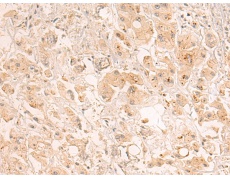

IHC positive control: |

Human lung cancer |

IHC Recommend dilution: |

20-100 |